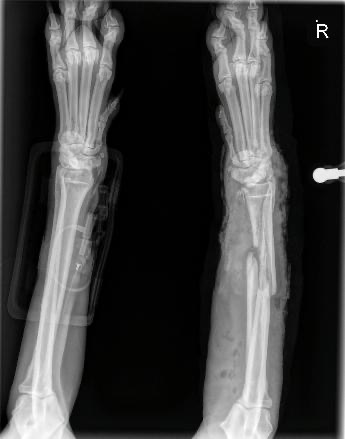

Hey I’m Kane, I’m from London, I was road tripping across the US with my dog, Lucy. We made it from NYC north west all the way to San Fran. We were on our way back through the south when she was hit by a car at a campsite in Lake Whitney state park, Texas.

She got emergency care in Texas, I then drove to NYC as we were given the all clear to fly by the Texas vet. When we got to NYC and found a vet they said she definitely can’t fly. The wound is too large and needs time to heal before she can safely travel. It’s been very overwhelming and I know no one in this city which is making it even harder.